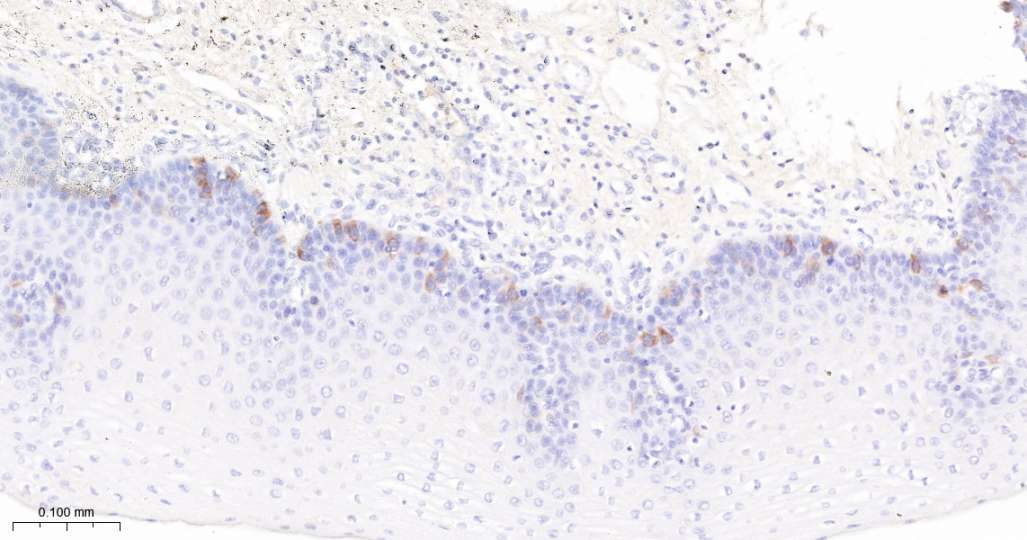

Immunohistochemical analysis of paraffin embedded Human tonsil tissue slide using IHC0690H (Human Cyclin B1 Kit).